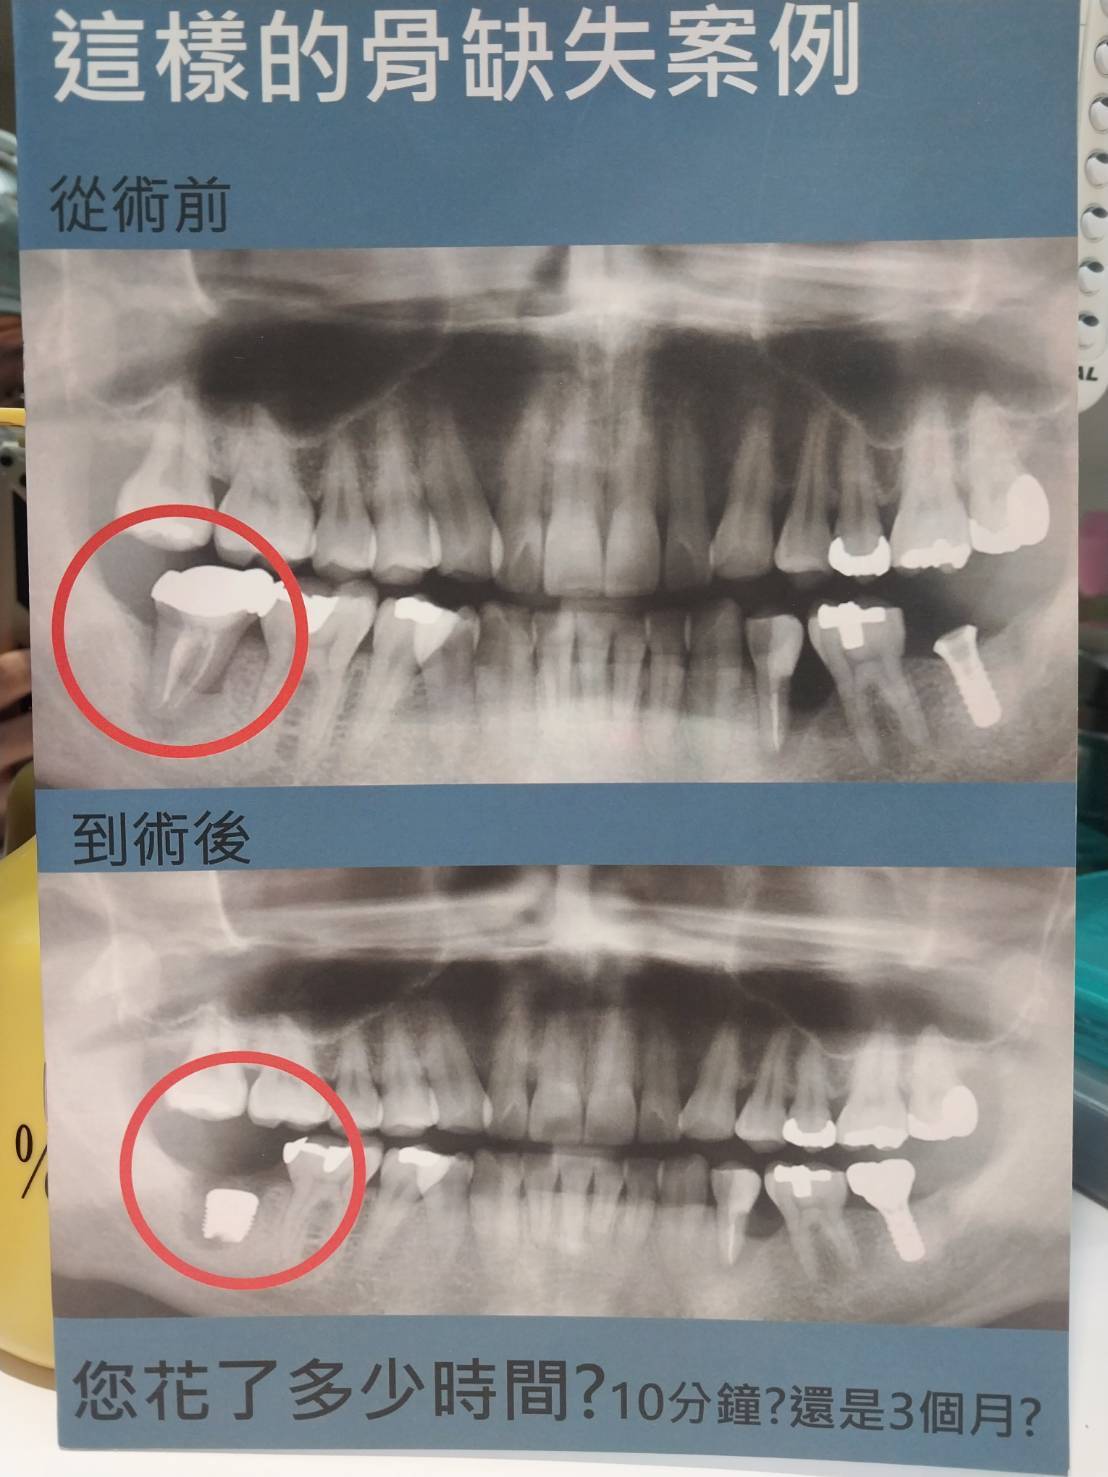

▲骨缺失案例,您花多少時間?

因為,嚴重骨缺失的案例,他牌要即拔即植會失敗,所以醫師通常會跟患者說這很挑體質。

Osseofuse的植體,讓醫師看到四個球(或十個球)就能確認可以立即植牙,甚至初級穩度可以輕鬆達40牛頓,也可以接癒合帽或臨時假牙。

★ 總療程時間:3~4個月就完成。